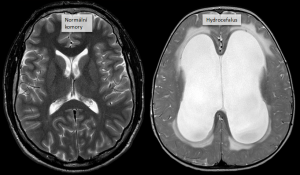

Hydrocefalus je termín označující nadměrné hromadění mozkomíšního moku v mozkových komorách. Přebytečný mok způsobuje tlak na mozkovou tkáň, a tím poškození mozku až s trvalými následky.

Mozkomíšní mok vzniká v mozkových komorách, protéká přes mokovod do páteřního kanálu a na povrch mozku (do tzv. subarachnoideálního prostoru), kde se vstřebává do žilního řečiště. Mozkové komory obsahují různé množství moku v závislosti na věku. Za den se celkové množství přibližně 3x kompletně obmění.

Hydrocefalus může být způsoben jednou či několika příčinami. Tradičně se rozděluje na dva typy:

Diagnostickým cílem je zobrazení komorového systému CT vyšetřením nebo magnetickou rezonancí. U kojenců je možné využít ultrazvuk.

Léčba hydrocefalu je pouze chirurgická. V zásadě existují dvě možné operace – ventrikulostomie III. komory a zavedení ventrikuloperitoneální zkratu.